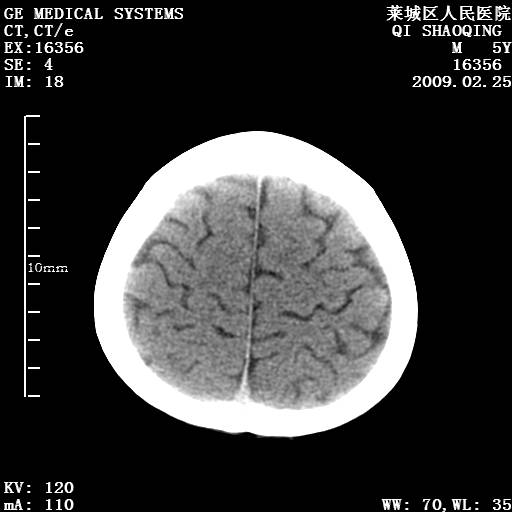

以下是引用wangzhengyuan在2009-2-28 10:22:00的发言:[br]甲状旁腺功能减退引起的脑改变.

以下是引用zsl6918在2009-2-28 10:17:00的发言:[br]首先考虑甲状旁腺功能低下所致,可结合实验室检查明确.另外需除外先天性宫内感染所致.

以下是引用余辉在2009-3-1 9:35:00的发言:[br]患者明显的肢体及智力改变,不支持fahr病,多考虑甲旁低,有可能伴有甲低(呆小症).进一步检查。